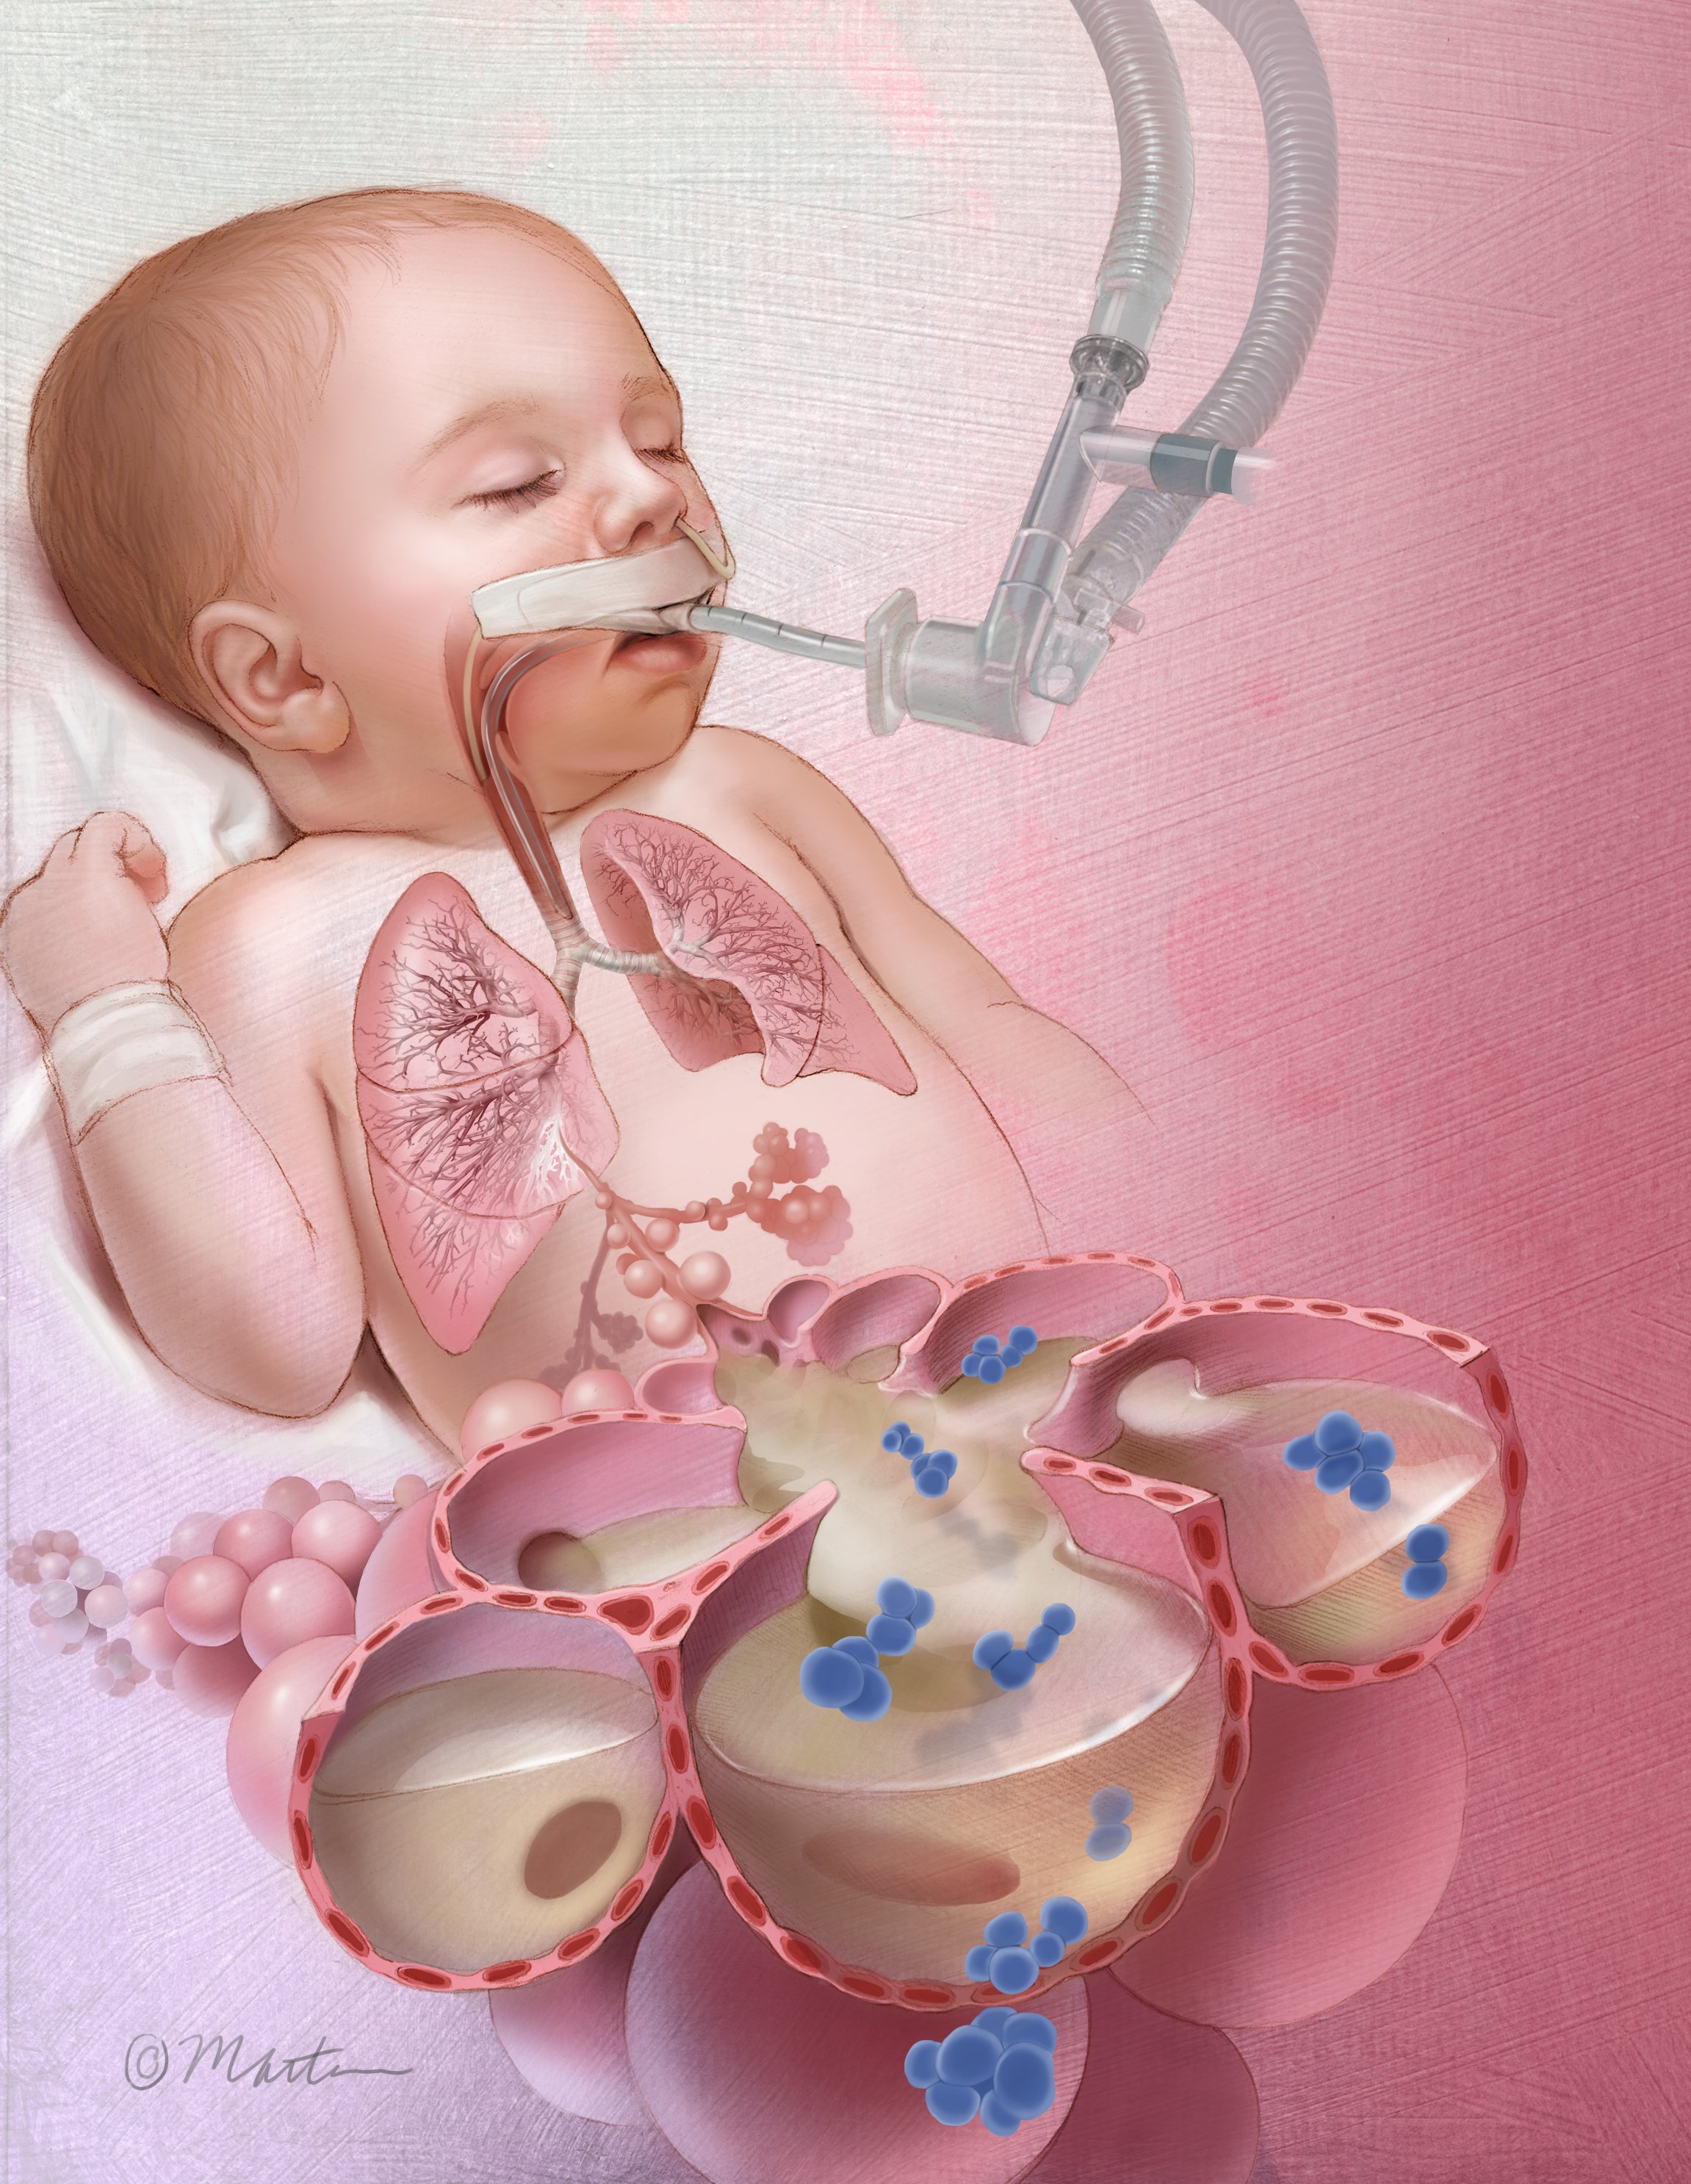

Ventilator-associated pneumonia (VAP) in Children